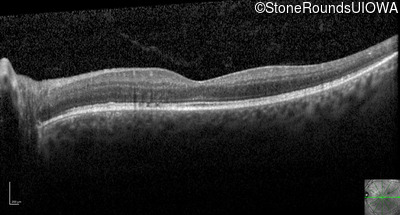

Optical Coherence Tomography - Left - 20/20 -1

Exemplar / OCT Stack